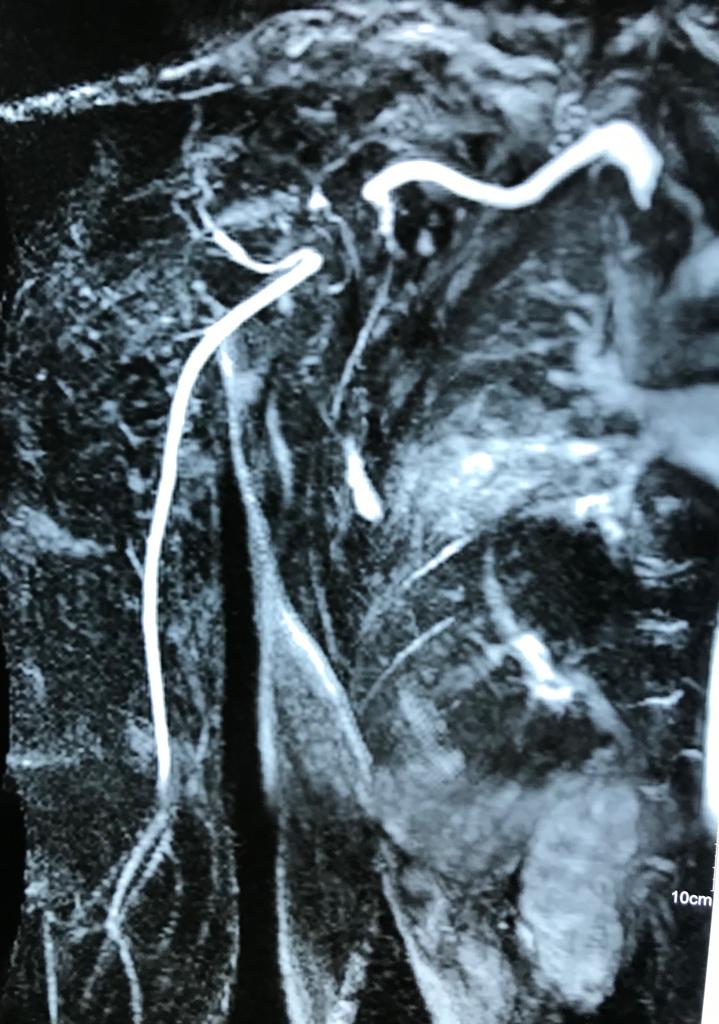

Angioresonancia periférica (miembro superior derecho).

Pacientes con luzación glehumeral anterior y fractura diafisiaria del humero, de un mes de evolución. Se complica con una oclusión de un segmento de la arteria subclavia-axilar, secundaria a trombosis.